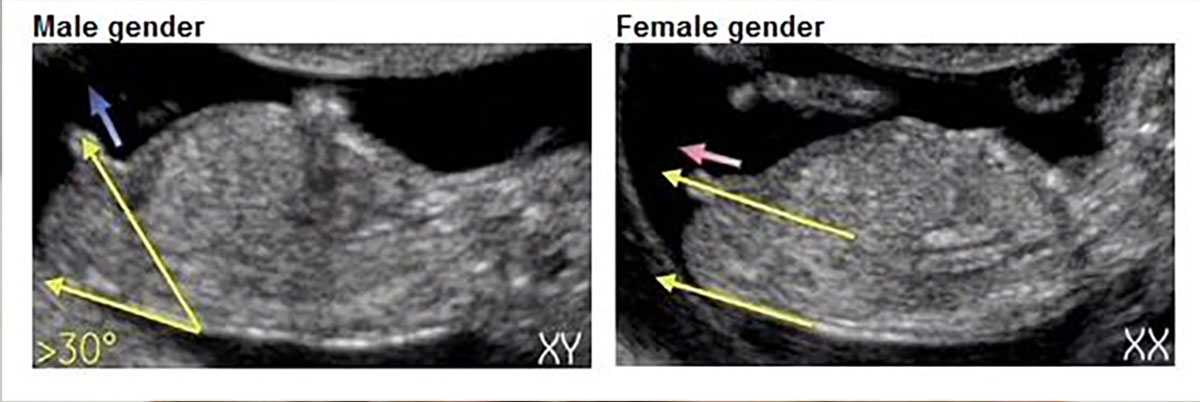

Пол на 14 неделе беременности по узи

Пол на 14 неделе беременности по узи 88 фото